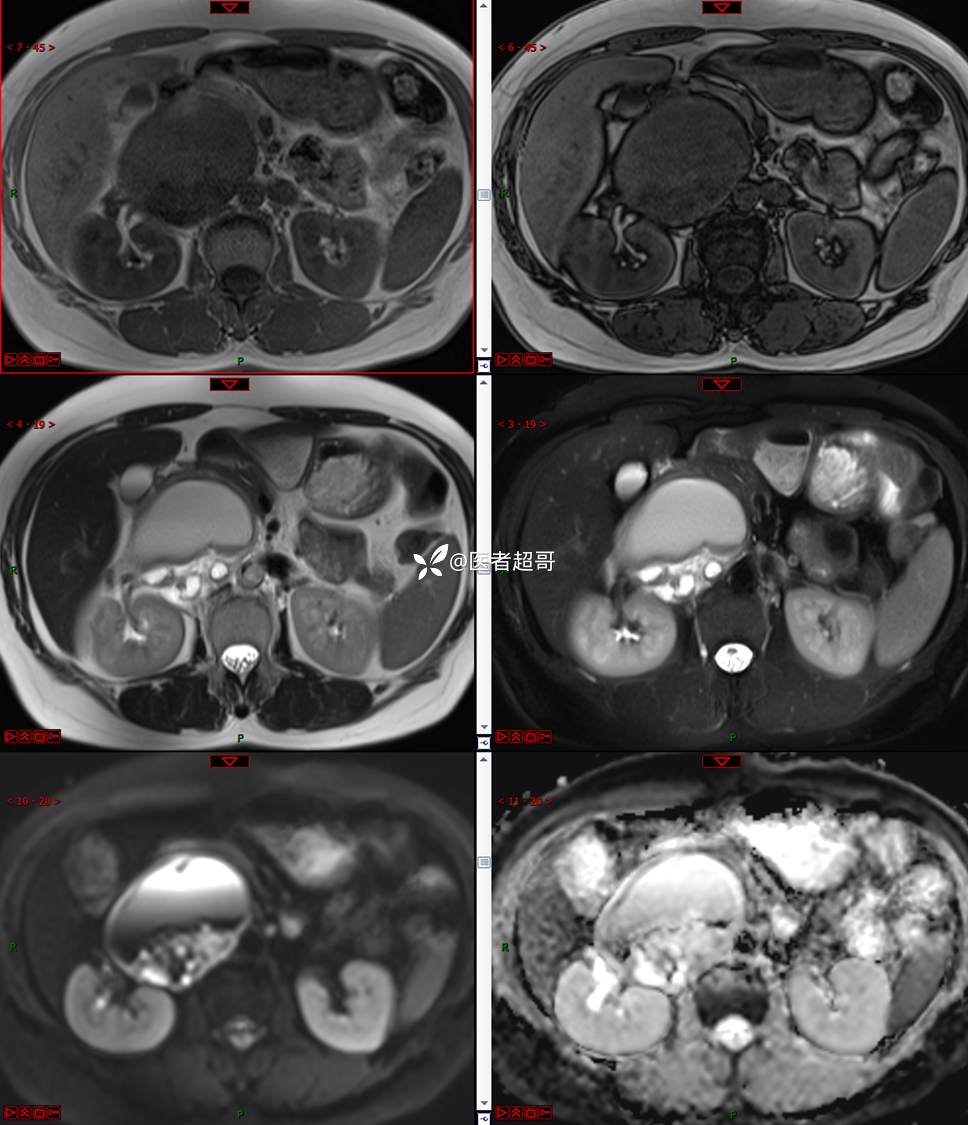

【影诊笔记671】定位有难度,究竟是腹腔内or腹膜后,请先定位,再定性!有结果~~~

hyy838 推荐女,52岁

主诉:查体发现腹部肿物1周。

现病史:患者1周前于我院查体发现右侧腹部肿物,无腹痛、腹泻、便血,无恶心、呕吐,患者为求进一步治疗,遂就诊于我院,门诊以“腹部肿物”收入院。患者自患病以来睡眠可,精神可,饮食可,小便无明显异常,体重无明显变化。

专科检查:腹部平坦,腹肌软,无压痛及反跳痛,无包块,肝脾无肿大,Murphy征阴性,腹部叩鼓,肝脾双肾无叩痛,移动性浊音阴性,肠鸣音正常。我院 肝胆胰脾肾彩超提示:脂肪肝、腹腔内囊实性团块,建议进一步检查。